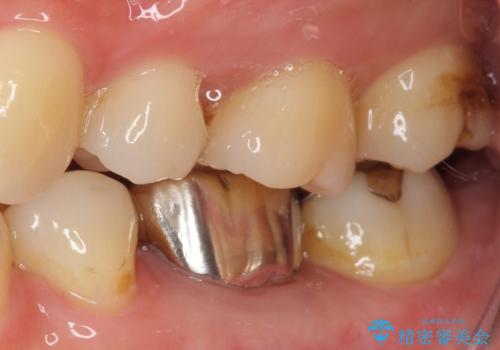

目立つ銀歯をオールセラミッククラウンで自然に|20代女性の審美補綴症例

患者様は根管治療のやり替えは希望されなかったため、ファイバーコア+オールセラミッククラウンによる補綴治療を行いました。

精度の高い補綴治療は、

・歯と被せ物のすき間が少ない

・汚れが溜まりにくい

という特徴があり、二次う蝕(被せ物の中で再発する虫歯)のリスクを低減できます。

見た目だけでなく、将来の歯の健康を守ることも大切にした治療を行っています。